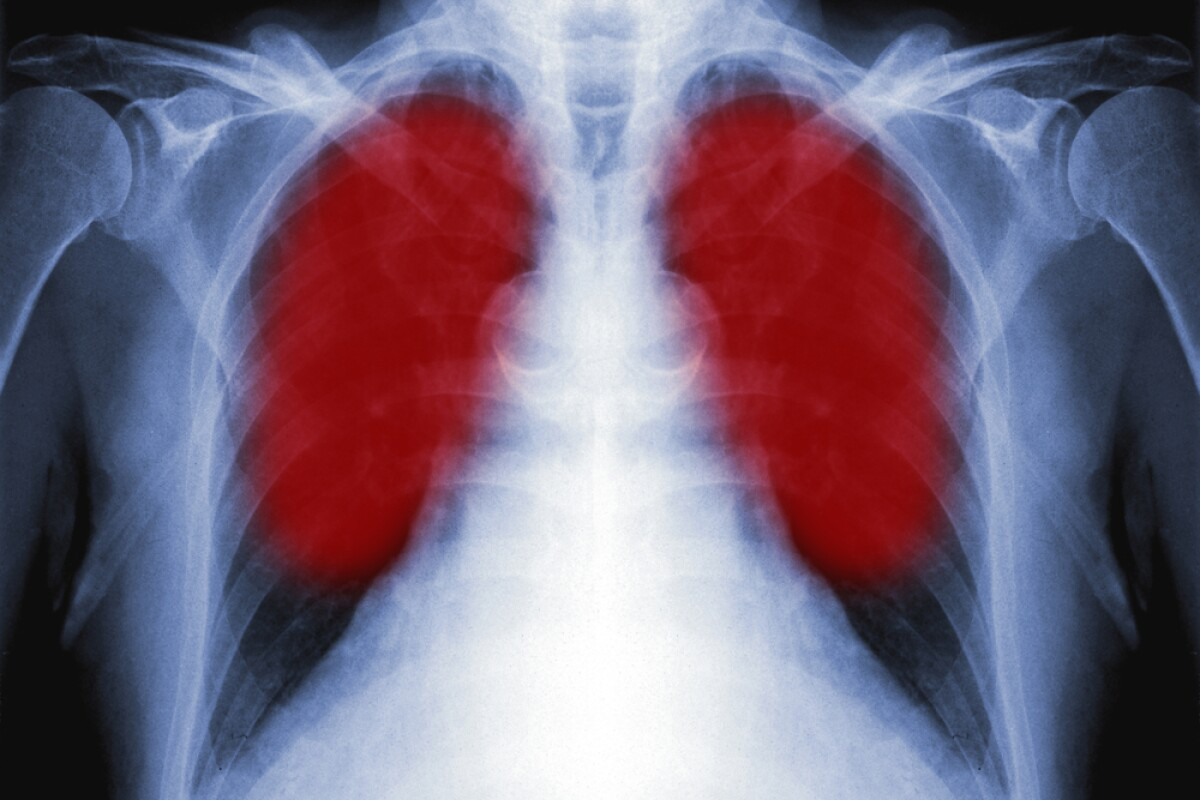

Why Chest X-Rays Miss Lung Cancer: The 20-25% Gap

It’s important to know why chest X-rays miss lung cancer in 20-25% of cases. Chest X-rays are useful in medical checks but have limits. These limits can cause some cancers to go undetected.

Size Limitations: Small Tumors and Detection Thresholds

One big reason chest X-rays miss lung cancer is the size of the tumor. Tumors that are small, often in the early stages, can’t be seen on a chest X-ray. Studies show that tumors under 1 cm are hard to spot with this method.

This means patients with small tumors might get false-negative results. This delay can hold off diagnosis and treatment.

Anatomical Obscuration: When Cancer Hides Behind Structures

Another reason lung cancer is missed is because of where the tumor is. Tumors can hide behind bones, the heart, or other chest structures. This makes them hard or impossible to see on a standard X-ray.

This is more common for tumors in complex areas or those hidden by dense structures.

First Stage Lung Cancer and X-Ray Detection Challenges

Early-stage lung cancer detection with chest X-rays is tough. It affects how well patients do. Even with new tech, X-rays struggle to spot lung cancer early.

Detection Rates for Early-Stage Lung Cancer

Research shows chest X-rays catch early-stage lung cancer less often. Tumors are small at this stage, making them hard to see. To improve, we need better tools and to understand these issues better.

Timeline: Detection Sensitivity Over Time

Studies show chest X-rays’ ability to find lung cancer changes over time. They’re about 76% accurate a year before diagnosis. But this drops to 60% two years before. This shows how hard it is to catch cancer early and why we need better ways to check for it.